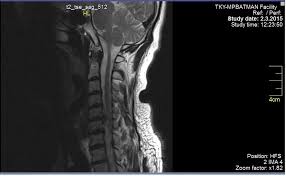

Boyun Fitigi